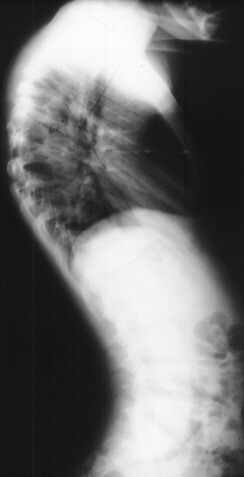

In preparation for spinal fusion for stabilization of this kyphoscoliosis he underwent a MRI of the brain cervical and thoracic spine and CT of the thorax. The brain and cervical spine showed no evidence of tumor. The lower cervical and upper thoracic canal was enlarged without evidence of cord compression, a finding consistent with dural ectasia . There is soft tissue protrusion into the thoracic canal that may resemble a dumbbell lesion.

Coinciding with current literature recommendations for treatment of severe dysplastic kyphoscoliosis, the patient underwent an Anterior-Posterior spinal fusion from T1-T10. The scoliosis was corrected to 21 degrees and kyphosis to 34 degrees. The procedure was augmented with a rib strut graft and was tolerated well. No neurologic complications occurred and the patient developed a solid fusion by one year without progression of the curvature. He is currently 5 years post-op playing in sports and without pain.